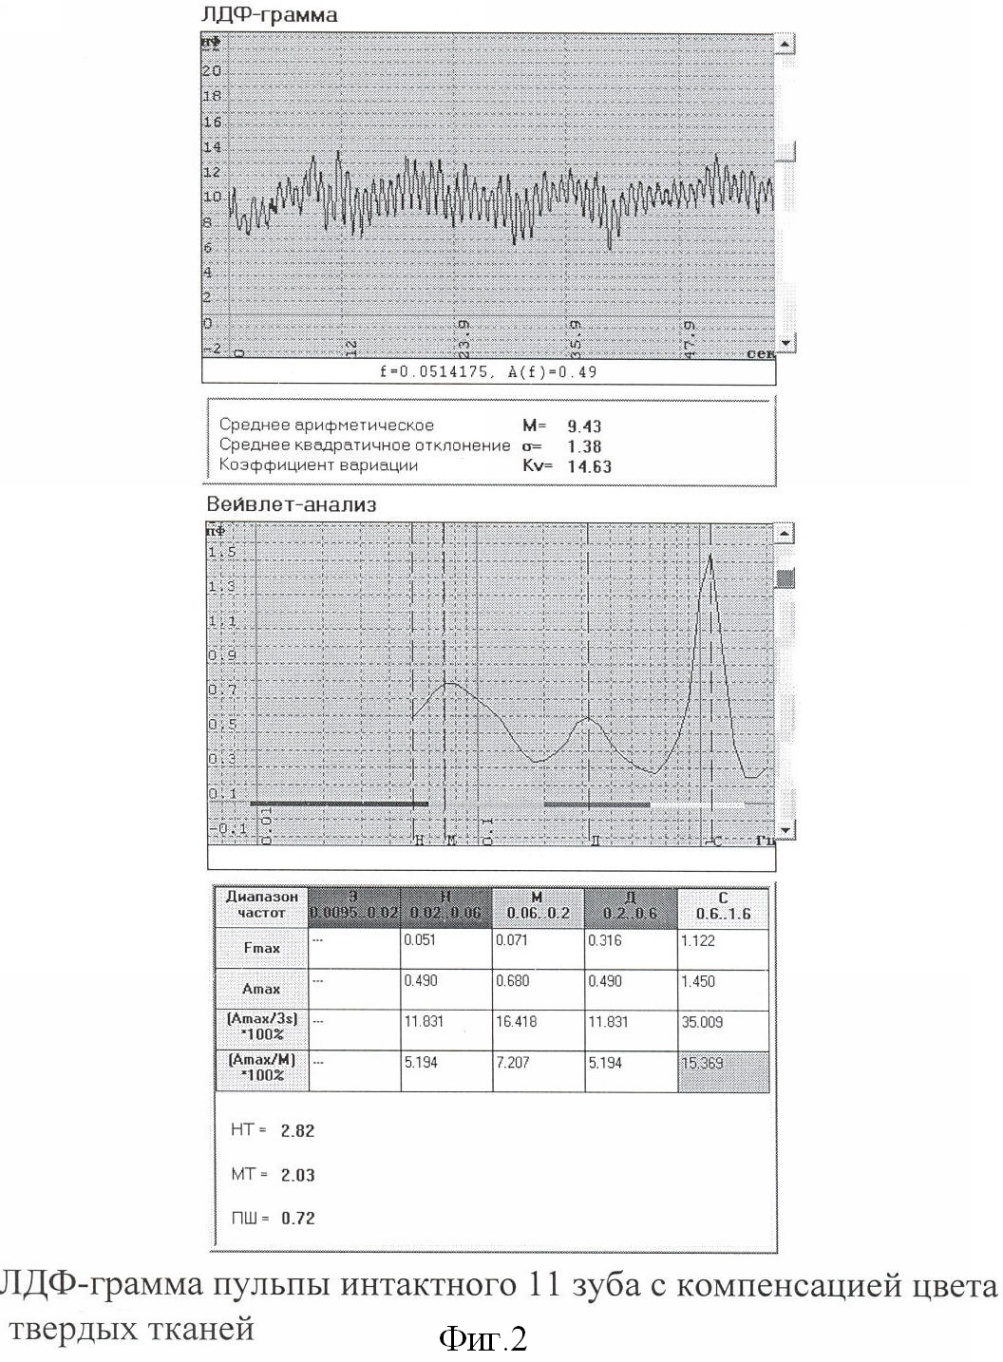

При регистрации ЛДФ-граммы традиционным способом ПМ составил 1,4 ПЕ (фиг.1.), а с помощью цветовой компенсации твердых тканей зуба – 9,43 ПЕ (фиг.2.). При анализе амлитудно-частотного спектра с помощью Вейвлет-преобразования видно, что сердечный ритм при цветовой компенсации зуба превышает таковой без аппаратной компенсации в 20,7 раза, дыхательный – в 4,9 раза и миогенный – в 17 раз (фиг.1, 2.).

Для сравнительной оценки полученных данных в эксперименте проводили регистрацию ЛДФ в пришеечной области на 2 мм выше десневого края в зоне предполагаемого выступа пульпы депульпированного 36 зуба с предварительным выставлением биологического нуля традиционным способом (белая фторопластовая пластина) (фиг.3.). На ЛДФ-грамме видно, что уровень сигнала соответствует 1,16 ПЕ. На фиг.4 после воздействия на твердые ткани зуба когерентным лазерным излучением и обработки сигнала методом компенсации цвета зуба с верхней трети коронки на допплерограмме значения показателя микроциркуляции (ПМ) составили 0,01 ПЕ, что и соответствует биологическому нулю.